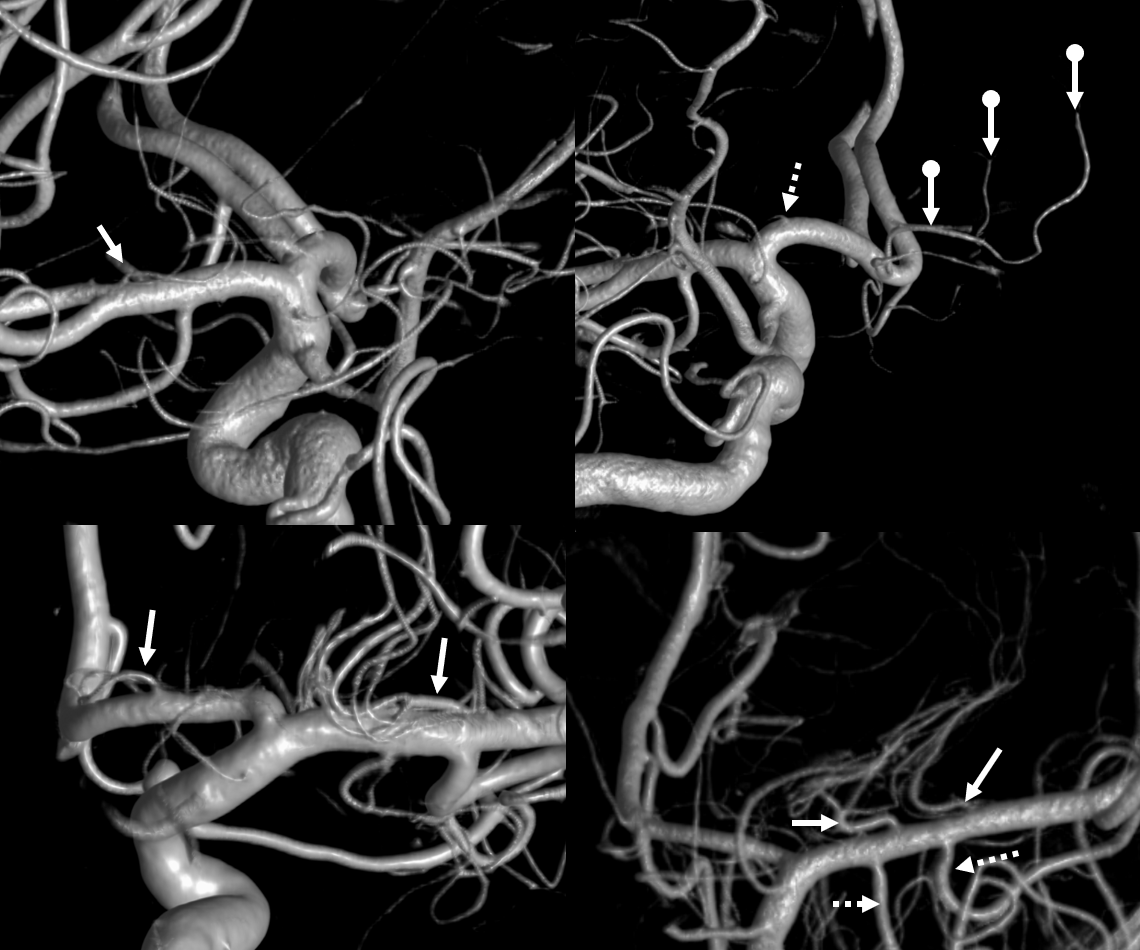

Below there are three patients. First one (top two images) shows dominant lateral group on one side (arrows) with correspondingly small medial group (dashed arrow), while on the other side the medial group (Heubner) is highly dominant (ball arrows). Bottom left — another patient, co-dominant medial and lateral groups (arrows). Bottom right — third patient, dominant lateral group again with two trunks (arrows). Also rare “duplicated” anterior temporal branches (dashed arrows)